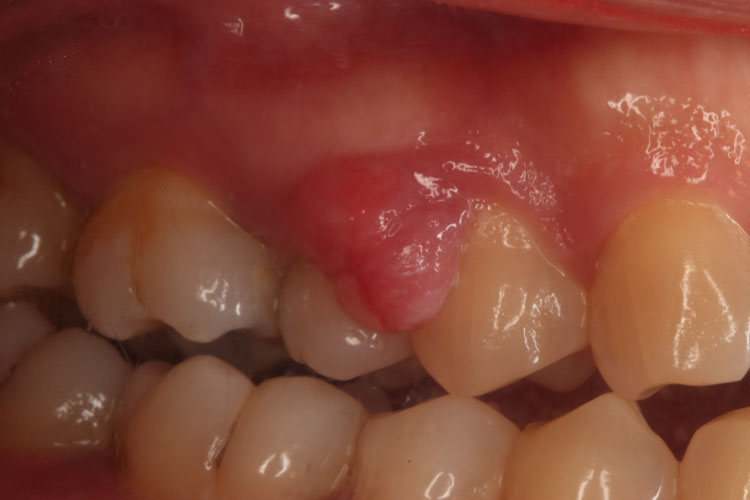

牙龈瘤:通常呈圆形、椭圆形,有时呈分叶状,看起来像囊肿,大小不一,从数毫米至1-2厘米。带蒂者,如息肉状,无蒂者,基底宽广。